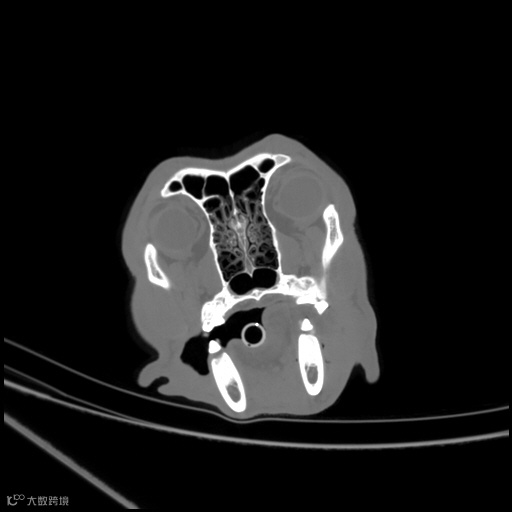

图像中能够显示的最小细节。观察图像中能否清晰识别小的解剖特征,并排除模糊或失真的情况。高分辨率图像可以清晰地显示小的解剖结构和病变。

肺部高分辨

鼻腔黏膜/鼻甲高分辨